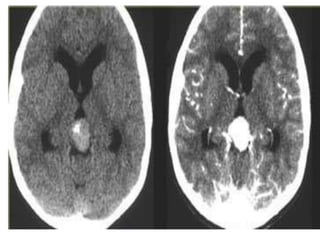

Axial nonenhanced CT shows a large pineal region mass with resultant hydrocephalus ,

the pineal calcifications are exploded toward the periphery (arrows)

b) Pineoblastoma : -Highlymalignant PNET (Primitive Neuroectodermal Tumors) -In patients with trilateral retinoblastoma, Pineoblastoma may develop in patients with familial and or bilateral retinoblastoma -(Exploded calcifications) along outside of mass (peripherally), unlike germinoma which engulfs and induces calcification of the pineal gland -Dense enhancement -Larger, more heterogeneous with much greater propensity for local invasion and CNS dissemination

• 60.

Axial nonenhanced CTshows a large pineal region mass with resultant hydrocephalus , the pineal calcifications are exploded toward the periphery (arrows)